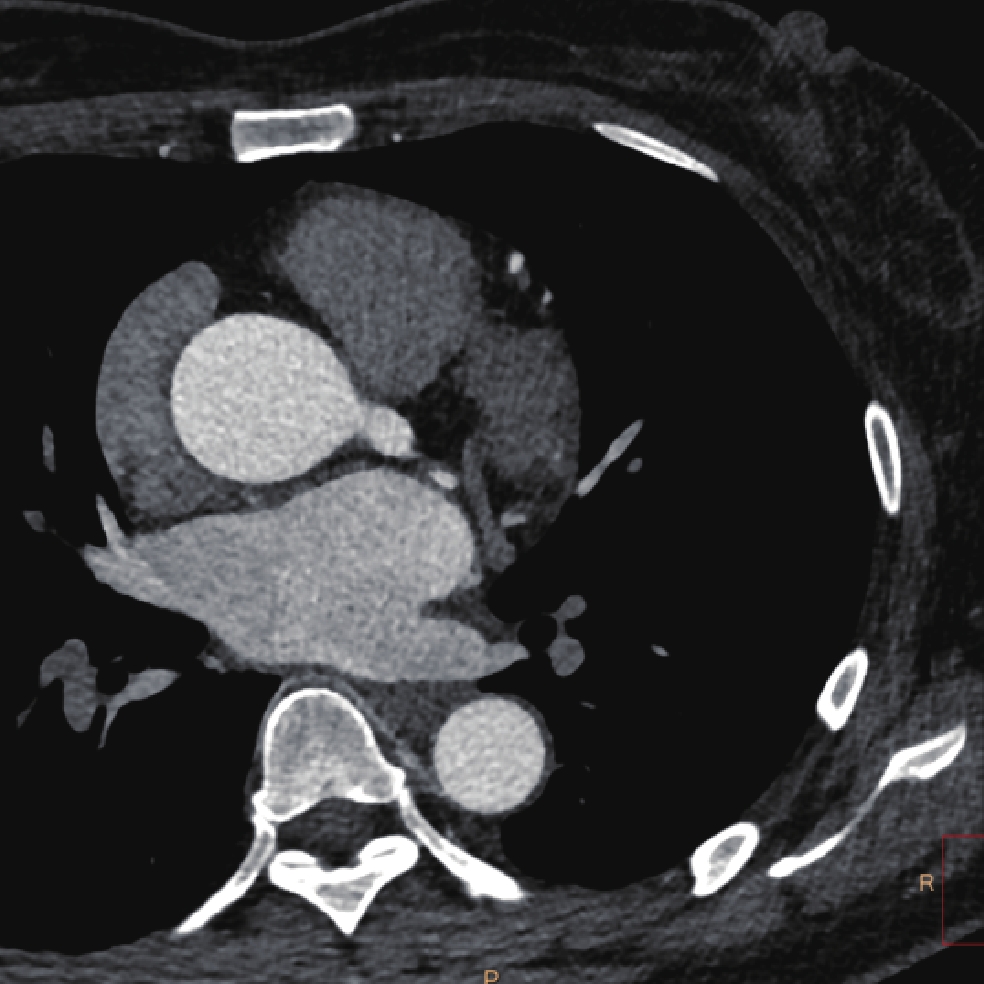

• 摘要: 目的:探讨不同扫描模式对胸主动脉CTA图像质量和辐射剂量的影响。方法:回顾性分析未应用心电门控技术的30例胸主动脉CTA(组1,对照组),使用回顾性心电门控的30例冠脉CTA重建舒张期(组2)和收缩期(组3)时相,30例应用宽曝光脉冲前瞻性心电门控技术(组4)共4组图像的质量和辐射剂量。分别记录、计算4组的图像质量客观指标CT值、噪声、CNR和辐射剂量指标CTDIvol。对图像质量进行四分法主观评价。对主客观指标分别统计分析。结果:客观指标CNR组1与组2、3、4均有差异,组2、3、4间均无差异;主观评分两两比较组2~4显著高于组1,组2~4间无差异。非门控组(组1)、回顾门控组(组2和组3)和前瞻门控组(组4)的CTDIvol分别为13.70(11.87,16.58)、12.62(10.03,15.01)、11.54(8.92,15.56),差异无统计学意义。结论:在胸主动脉CTA中推荐使用窄曝光脉冲的前瞻性心电门控收缩期或舒张期扫描,可显著提高胸主动脉心脏段图像质量并降低辐射剂量。

Abstract: Objective: This study aimed to compare the effects of different scanning modes on image quality and radiation dose in thoracic aortic computed tomography angiography (CTA). Methods: The image quality and radiation dose of 30 cases of thoracic aortic CTA (Group 1, control group), 30 cases of retrospective CTA diastolic phase (Group 2) and systolic phase (Group 3), and 30 cases of wide-exposure pulse prospective electrocardiogram (ECG) (Group 4) were retrospectively analyzed. The CT value, noise, contrast-to-noise ratio (CNR), signal-to-noise ratio (SNR), and radiation dose (volume CT dose index CTDIvol) were recorded and measured. The image quality was evaluated subjectively using the four points method. The subjective and objective indicators were analyzed statistically. Results: No differences were observed in the objective indexes of noise, CNR and SNR among the groups. The subjective score of pairwise comparison of Groups 2~4 was significantly higher than that of Group 1, and no difference was observed among Groups 2~4. The CTDIvol values of the non-gated group (Group 1), retrospective gated groups (Groups 2 and 3), and prospective gated group (Group 4) were 13.70 (11.87,16.58), 12.62 (10.03,15.01), and 11.54 (8.92,15.56), respectively, without a statistically significant difference.